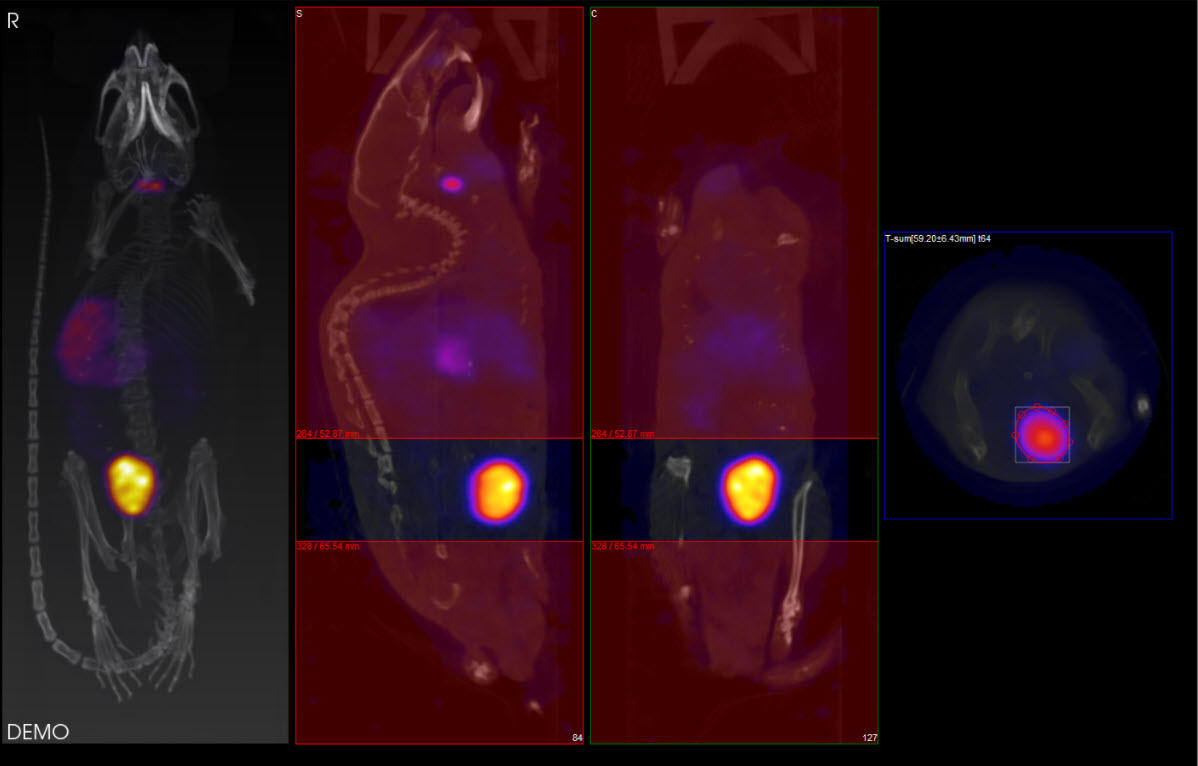

The ROI may be drawn in either the transverse (default), coronal, or sagittal plane. To toggle between these options, use the View menu in the Operator tab of the main menu.

In this example, using the default settings, the axial sliders determine the extent of the ROI in the axial direction. The region or pre-defined shape described below determines the bounds of the ROI in the transverse plane.